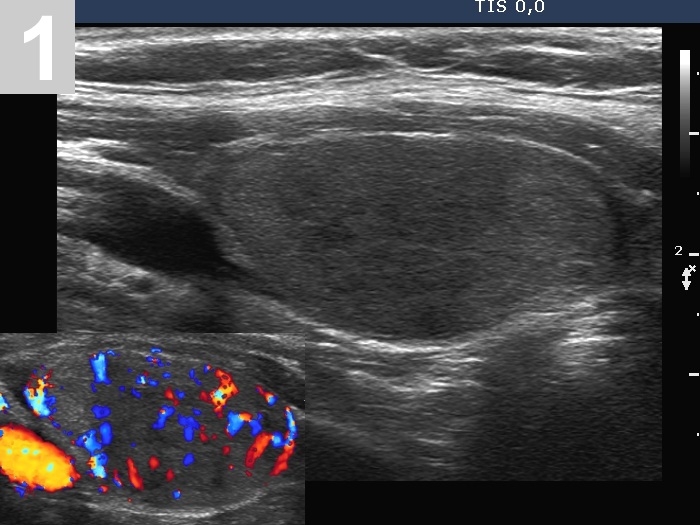

3 US of thyroid cancer

Pre- and postoperative ultrasound in thyroid cancers

Cases to be discussed on January 18, 2024